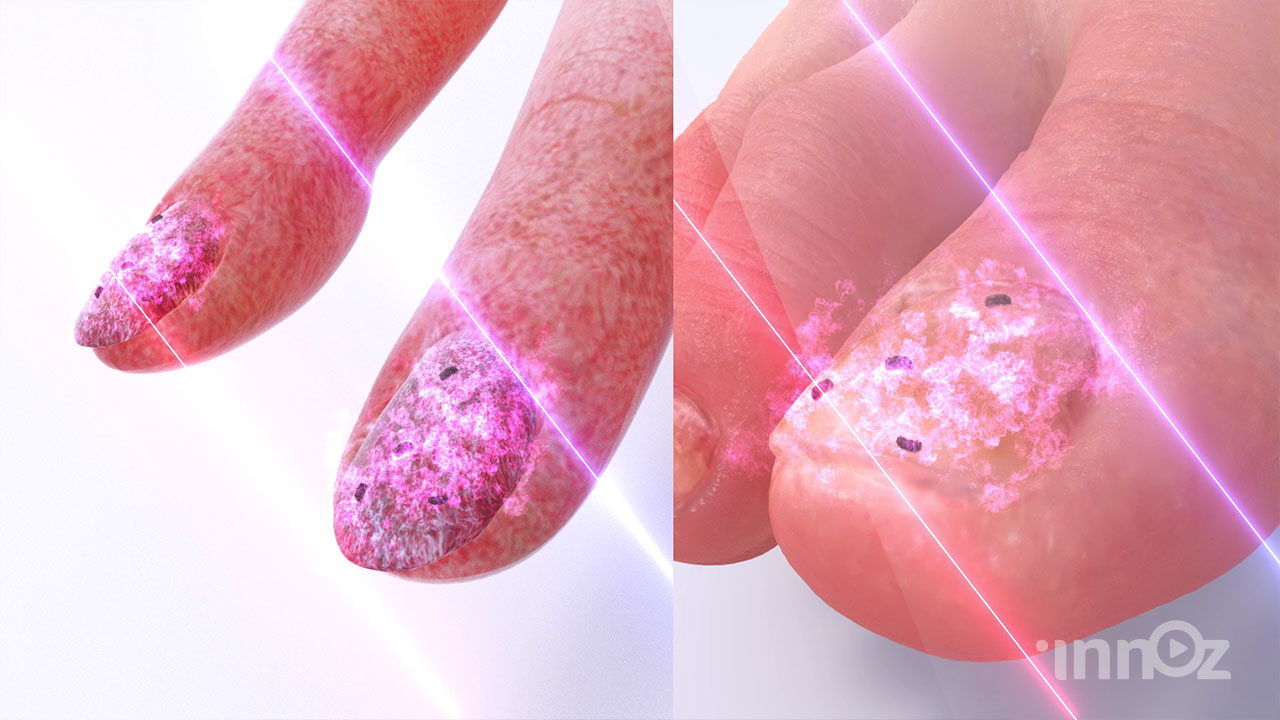

2023 쉬엔비 다이아코어등 고주파 치료기 전제품

2023 제이시스메디칼 고주파치료기 덴서티 영상제작

2022 텐텍 텐써마 고주파 의료장비 영상제작

쉬엔비

쉬엔비

쉬엔비

픽스메디코리아